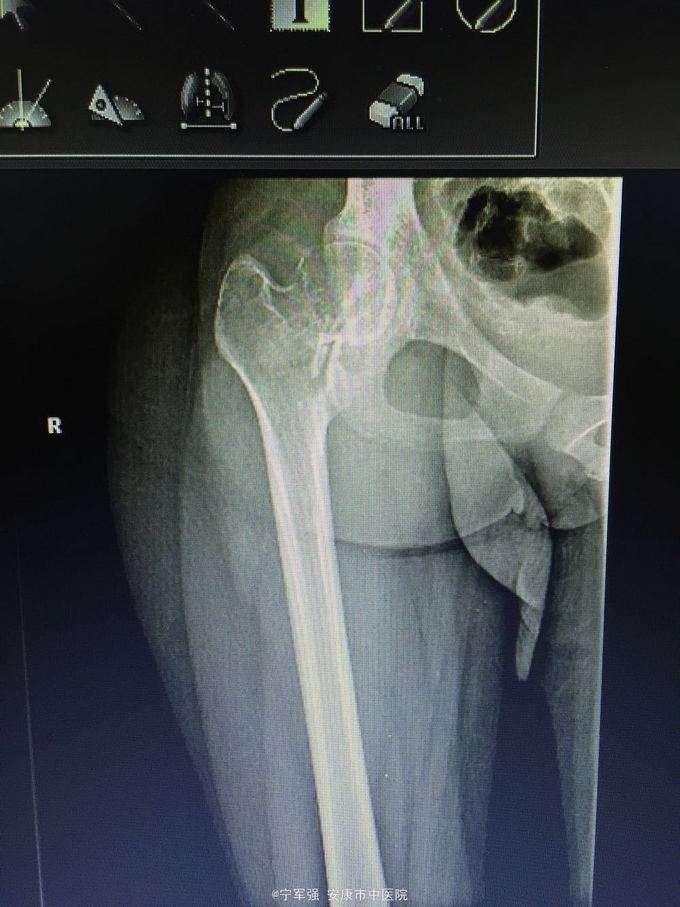

女性,20岁,外伤后右髋部疼痛不适活动受限 伤前身体尚可,5个月前有右大腿不适感,当时未行X线检查

查体:右髋部稍肿,局部压痛(+),纵向叩击痛阳性,右下肢短缩约1.5CM,末梢血运及皮肤感觉良好。 肿瘤标志物(-),碱性磷酸酶不高。

右股骨颈病理性骨折 处理:1.进一步完善检查髋关节MRI。 2.病检,确定性质; 3.消肿对症治疗; 4.择期植骨内固定术